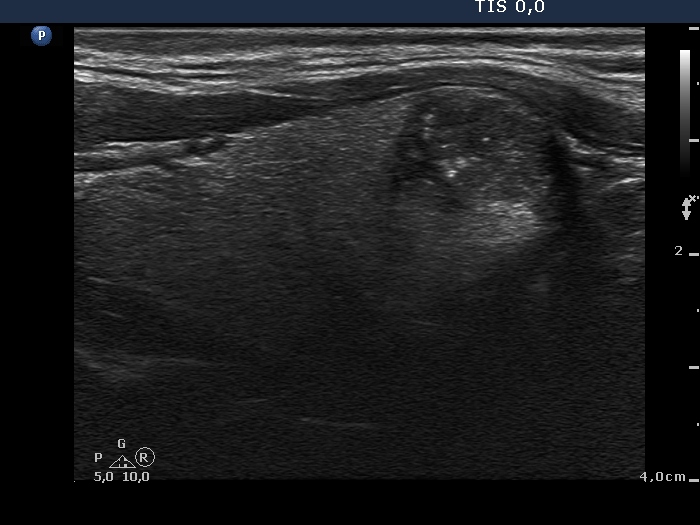

Follow-up examination 7 months after first visit (fourth and fifth third rows):

Clinical presentation: The patient underwent on radioiodine therapy. Post-therapeutic thyroglobulin level was 99.1 ng/mL while 3 months later the TG level fell only to 36.5 ng/mL. An ultrasound examination was initiated.

Palpation: a mass in the lower pole of the left thyroid bed was suspected.

Functional state: TSH 0.06 mIU/L, FT4 27.5 pM/L on daily 175 microgram levothyroxine.

Ultrasonography. There was no parenchyma according to the right thyroid bed. There were two hypoechogenic lesions in the lower pole of the left thyroid bed. Both were irregular in shape and presented cystic degeneration and microcalcifications. There was a reactive-type lymph node ventral to the previously described lesions.

Aspiration cytology was performed but was not diagnostic. The wash-out thyroglobulin-level exceeded 476 ng/mL.

Surgery was performed and 5 lymph nodes were removed. Three of them proved to be metastatic while 2 did benign, reactive-type nodes on histopathology.